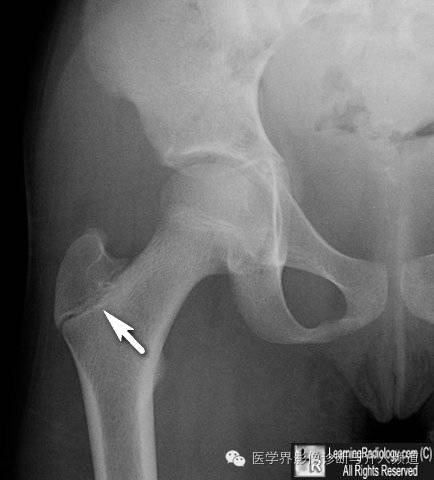

12、股骨大粗隆:股骨大小粗隆骨骺一般在15-20岁愈合。